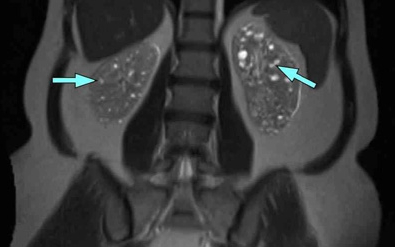

说到遗传病,常见就要数多囊肾了,它的遗传几率高达50%,又被叫做囊胞肾。因为遗传的关系,多囊肾的发病期分为婴儿型和成年型,前者比较少见,多是发生在青中年时期。除了肾脏有囊肿之外,胰腺、肝脏、大脑等器官也可伴随囊肿。